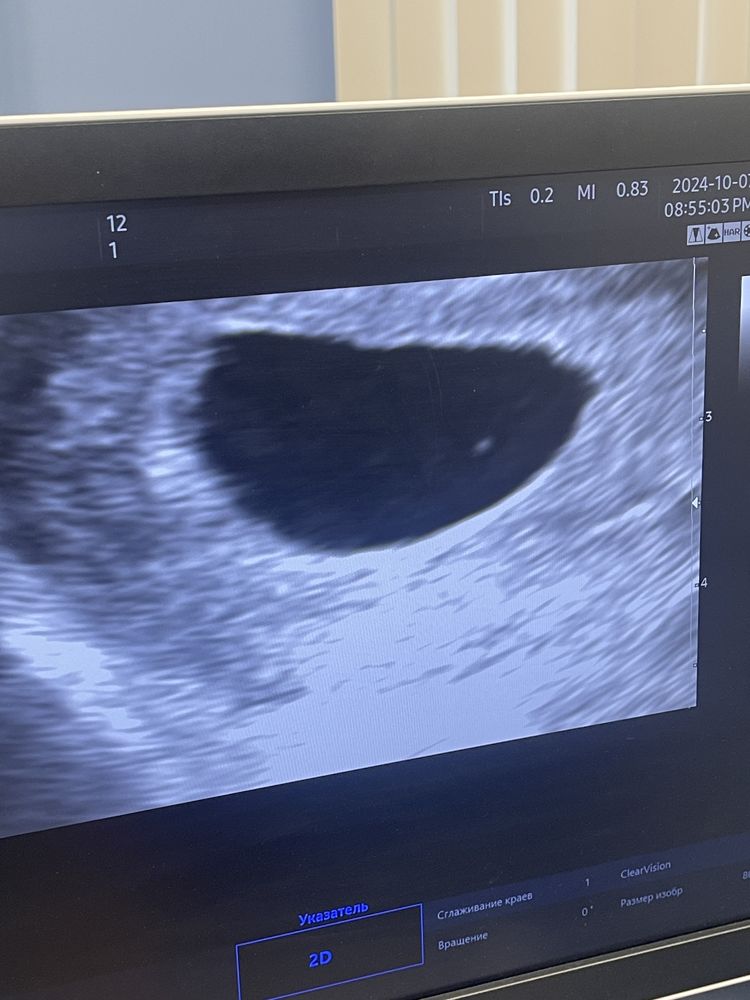

Анэмбриония под ?

К сожалению, шансов очень мало… По срокам уже должен быть виден эмбрион.

Ждут до 25 мм плодное яйцо... Шансы конечно минимальные :(

У меня хгч рос, а вот эмбрион не нашли. А желточных мешочек есть? Пя большое уже, конечно с большой долей вероятности не удачно(

6+5 уже много…. 🥲